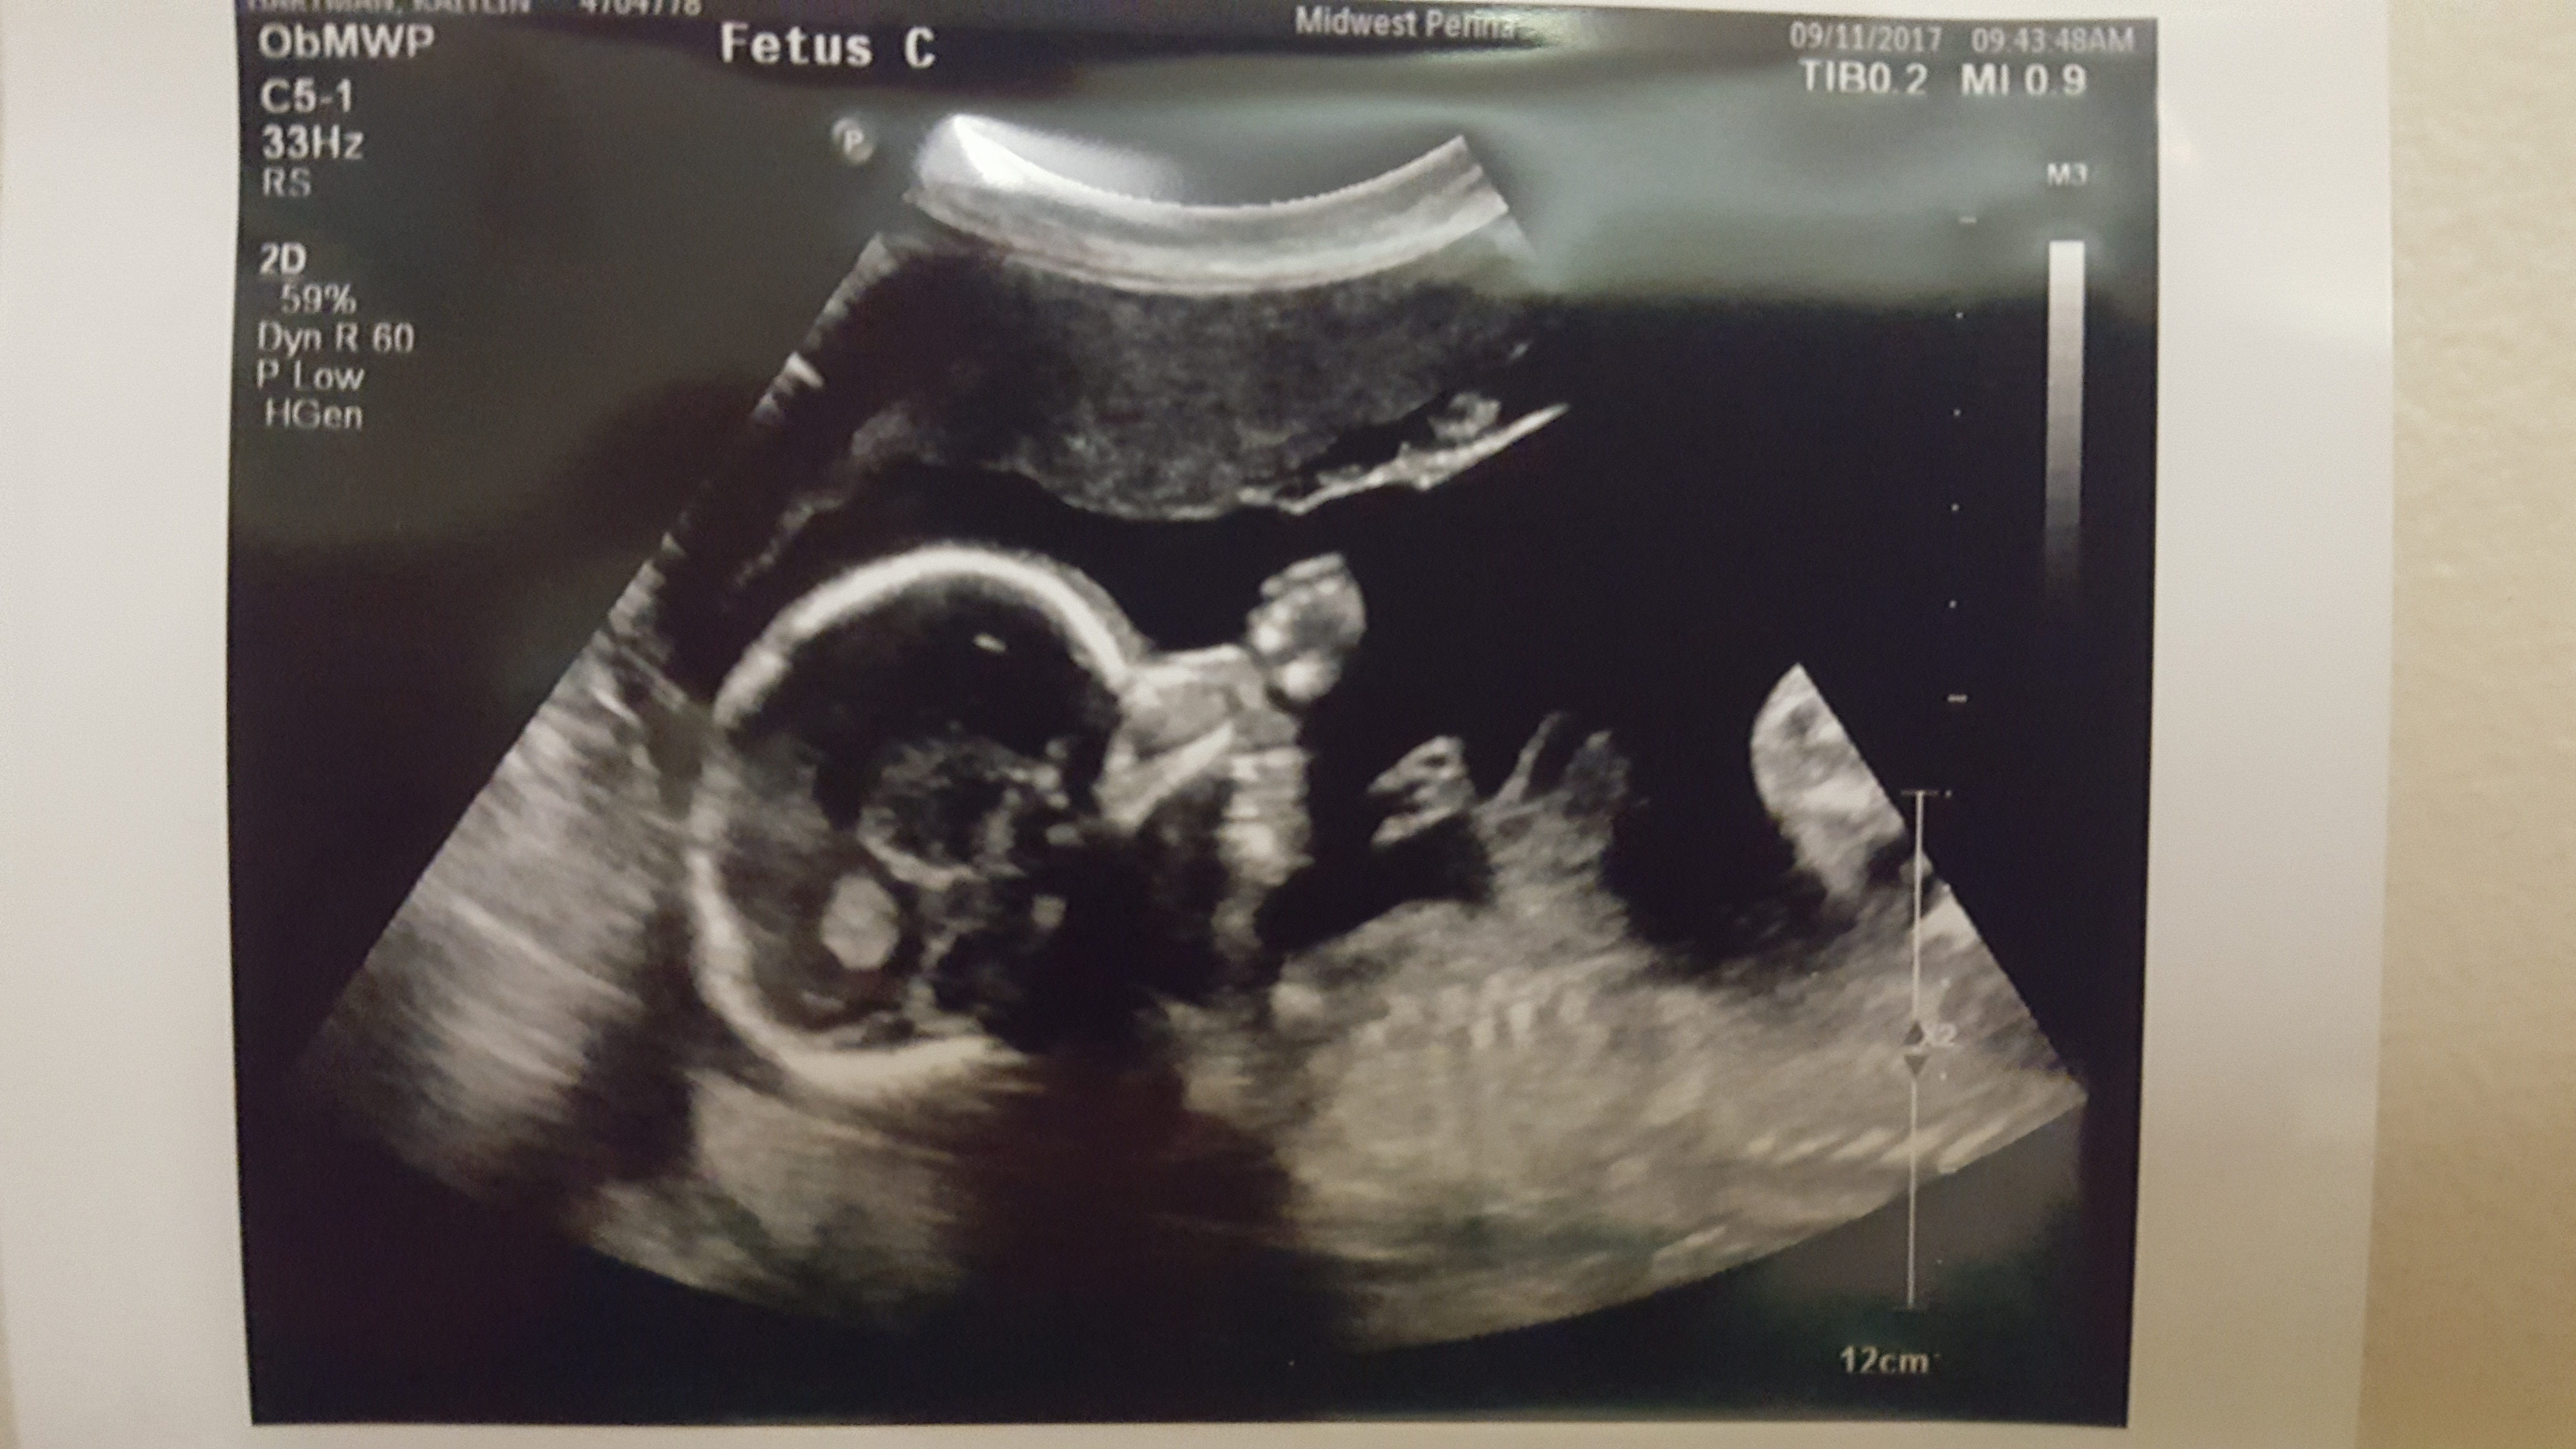

21 weeks (1)